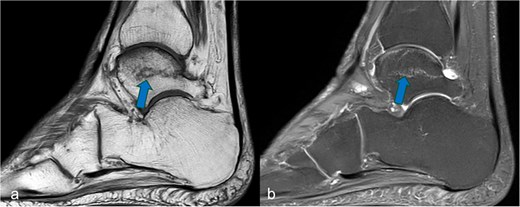

A history of trauma could be excluded. At a dose of 10 mg/week, the duration of MTX therapy was 11 years. An MRI scan performed due to severe pain of 7 on the VAS showed an edema zone with a demarcation line in the area of the right trochlea tali (Fig. 1). A DXA scan (Lunar Prodigy®) showed significantly reduced T-score values of −3.2 for the lumbar spine and −2.8 for the hips. In the area of the thoracolumbar junction, two consolidated sintering fractures were found in the conventional X-ray of the axial skeleton. At the time of the talus fracture, the patient was already undergoing antiresorptive osteoporosis therapy with a bisphosphonate. At 52 nmol/l, the vitamin D level was in the lower normal range at this time.

Sagittal MRI cross-sectional imaging showing (a) a T1-weighted and (b) a proton-weighted fat-suppressed image of the right tarsal bones. The ligamentous fracture in the trochlea tali was marked with arrows.